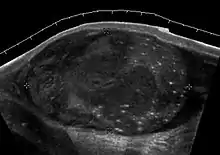

![]() Sonography of a normal testis. The normal testis presents as a structure having homogeneous, medium level, granular echotexture. The mediastinum testis appears as the

hyperechoic region located at the periphery of the testis as seen in this figure. | |

The normal adult testis is an ovoid structure measuring 3 cm in anterior-posterior dimension, 2–4 cm in width, and 3–5 cm in length. The weight of each testis normally ranges from 12.5 to 19 g. Both the sizes and weights of the testes normally decrease with age. At ultrasound, the normal testis has a homogeneous, medium-level, granular echotexture. The testicle is surrounded by a dense white fibrous capsule, the tunica albuginea, which is often not visualized in the absence of intrascrotal fluid. However, the tunica is often seen as an echogenic structure where it invaginates into the testis to form the mediastinum testis. In the testis, the seminiferous tubules converge to form the rete testes, which is located in the mediastinum testis. The rete testis connects to the epididymal head via the efferent ductules. The epididymis is located posterolateral to the testis and measures 6–7 cm in length. At sonography, the epididymis is normally iso- or slightly hyperechoic to the normal testis and its echo texture may be coarser. The head is the largest and most easily identified portion of the epididymis. It is located superolateral to the upper pole of the testicle and is often seen on paramedian views of the testis. The normal epididymal body and tail are smaller and more variable in position.